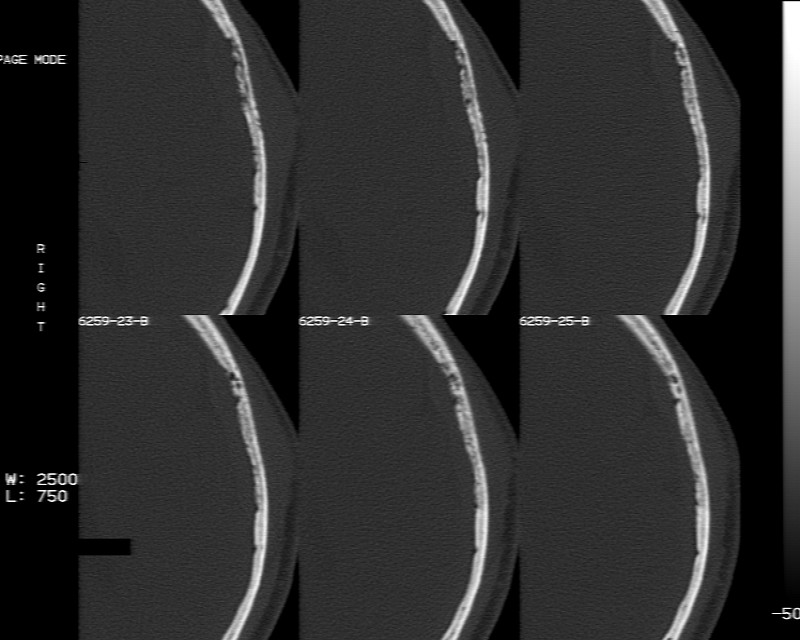

m70y, 2个月前发现左颞部有'包'隆起,近来自觉增大,无外伤无任何不适症状而就医,触诊包块质地较硬无移动无波动无皮温升高,胸片示右上肺陈旧结核....,ct扫描见左颞骨翼板局部内外骨板骨质破坏,似筛孔状,外板侧有骨膜线状增生,伴局部软组织丘状肿块,内板下梭形肿胀硬膜增厚翘起......颅内脑无异常.考虑骨良性病变 1.低度骨感染.   2.嗜酸性肉芽肿. 3.不排外骨结核...建议其穿刺活检,但患者失踪,追踪到结果定将公告.请大家分析.

左颞骨内板不光滑,密度减低,内板下可见新月形的软织密度影。脑实质轻度受压,外板外见膨胀形稍高密度影。考虑嗜酸性肉芽肿。建议增强扫描

骨质密度不均,骨质两旁均有软组织影,考虑嗜酸性肉芽肿可能性大,同时也不能除外转移瘤。